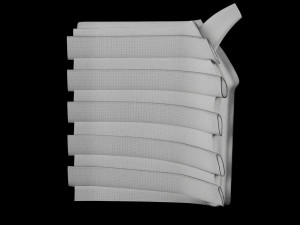

Breast anatomy histology detailed labelled precise to scale model 3D Модель

This is a 1:1 scaled model of right breast cut opened in sagittal plane to reveal its internal antomy and histology (schematic). The deeper parts and fascial layers are also depicted to give a very detailed approach to the model. The full layers starting from skin, nipple areola, till intercodtal muscles and ribs are also depicted.